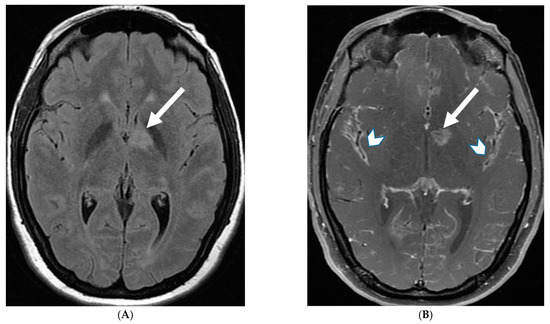

E. coli is another common neonatal and infantile cause of bacterial meningitis. There is characteristic diffusion restriction in the extra-axial collections along with ventriculomegaly and/or ventriculitis [74]. To note, extra-axial empyema is also common with S. pneumoniae, but occur in an older age group. Serratia marcescens and Citrobacter are two uncommon pathogens causing meningitis in neonates with fulminant disease course. They lead to large parenchymal abscesses with striated appearance on T2W images and foci of susceptibility. N. meningitidies causes typical gyriform cortical enhancement consistent with cerebritis predominantly involving the occipital lobes (Figure 12) [74].

Figure 12.

Axial DWI (A), axial SWI (B), sagittal T2 (C), axial ASL (D) and coronal T1 post contrast (E): 11-day-old female presented with seizures and lethargic. Restricted diffusion is noted in the sulci along the bilateral frontal convexities, concerning for meningitis (arrows). Curvilinear susceptibility in the extra-axial spaces of bilateral frontal convexities, consistent with thrombosed cortical veins (curved arrows). Cortical T2 hyperintensity is seen in the bilateral frontal and parietal lobes with corresponding hyperperfusion in keeping with extensive cerebritis (dashed arrows). Diffuse leptomeningeal and pachymeningeal enhancement is seen (open arrows). Overall features represent meningitis and cerebritis. Cerebrospinal fluid analysis: Group B streptococcus.